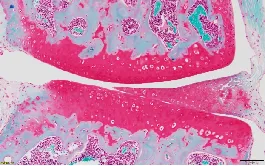

05.番红O染色